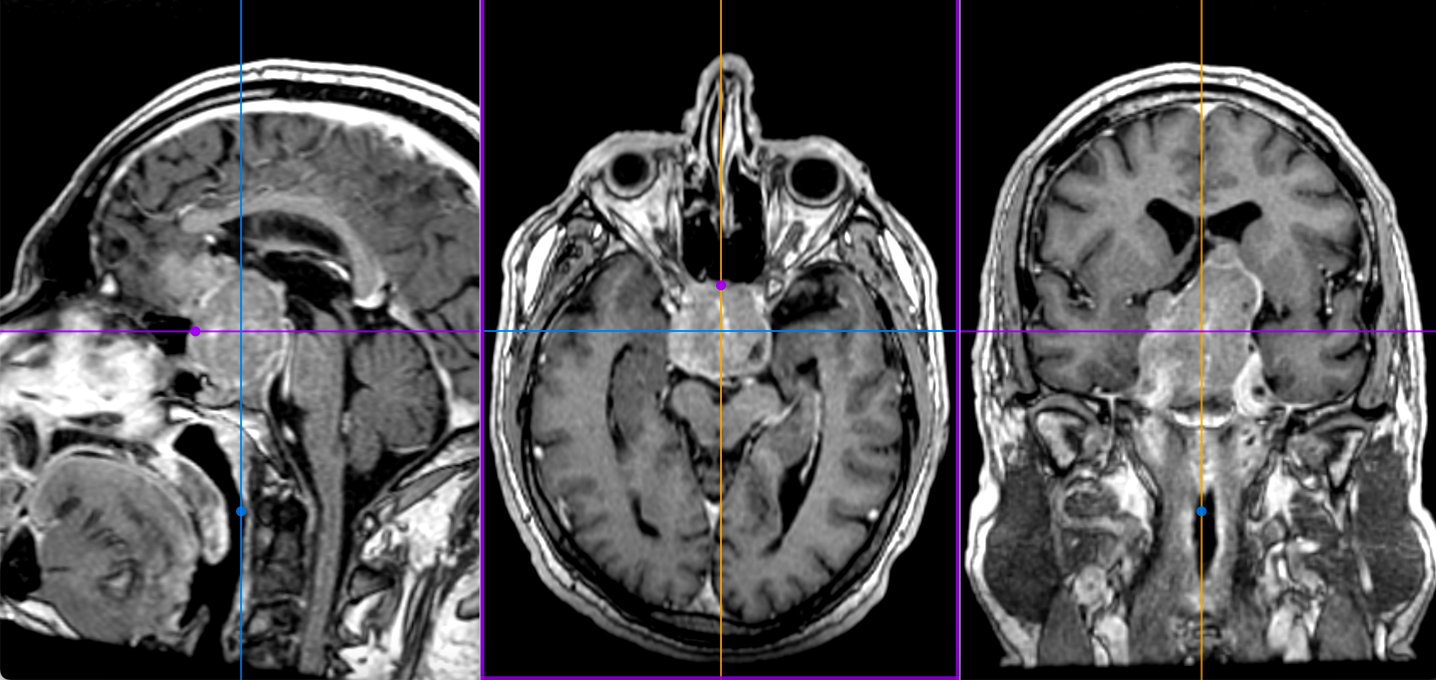

- Apoplexia pituitară reprezintă o complicație rară dar redutabilă a evoluției unui adenom hipofizar; se datorează unor modificări vasculare – un infarct al adenomului urmat de hemoragie, ceea ce determină creșterea bruscă și semnificatvă în volum a tumorii cu efect de masă pe nervii optici și structurile din jur. Clinic se caracterizează prin simptome brusc instalate și violente: cefalee, vărsături, tulburări de echilibru, scăderea bruscă a vederii. Reprezintă o urgență chirurgicală – doar operația efectuată rapid poate remite simptomele și salva vederea

Apoplexie pituitara

- Macroadenoamele hipofizare apar ca mase tumorale cu priza de contrast localizate la nivelul șeii turcești, eventual cu extensie superioară (supraselară) spre nervii optici sau, mai rar, inferioară, în sinusul sfenoid; de multe ori ele se pot extinde și lateral, în sinusurile cavernoase (structuri vasculare venoase formate în grosimea meningelui care mărginește lateral șaua turcească, prin care trec arterele carotide interne).